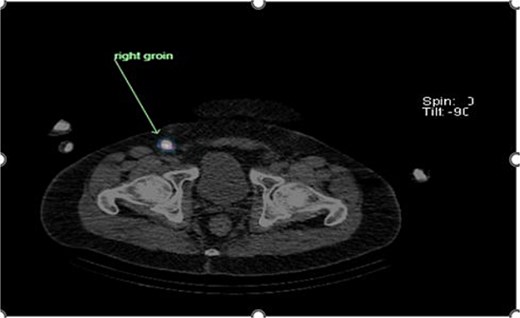

Preoperative lymphoscintigraphy was performed to detect the sentinel lymph node (Fig. 1), expecting it to be in the right inguinal region (Fig. 2). However, drainage to both the right axillary (Fig. 3) and inguinal areas was demonstrated. During surgery, a gamma camera confirmed drainage to both regions (Fig. 4). Blue dye was injected around the previous scar, and sentinel nodes were dissected guided by both blue dye and gamma camera for histopathology.

Unexpected drainage visualized toward the right axillary lymph nodes.

Histology showed no residual malignancy in the re-excision specimen. The right axillary node showed involvement by metastatic melanoma, while the groin lymph node was negative.